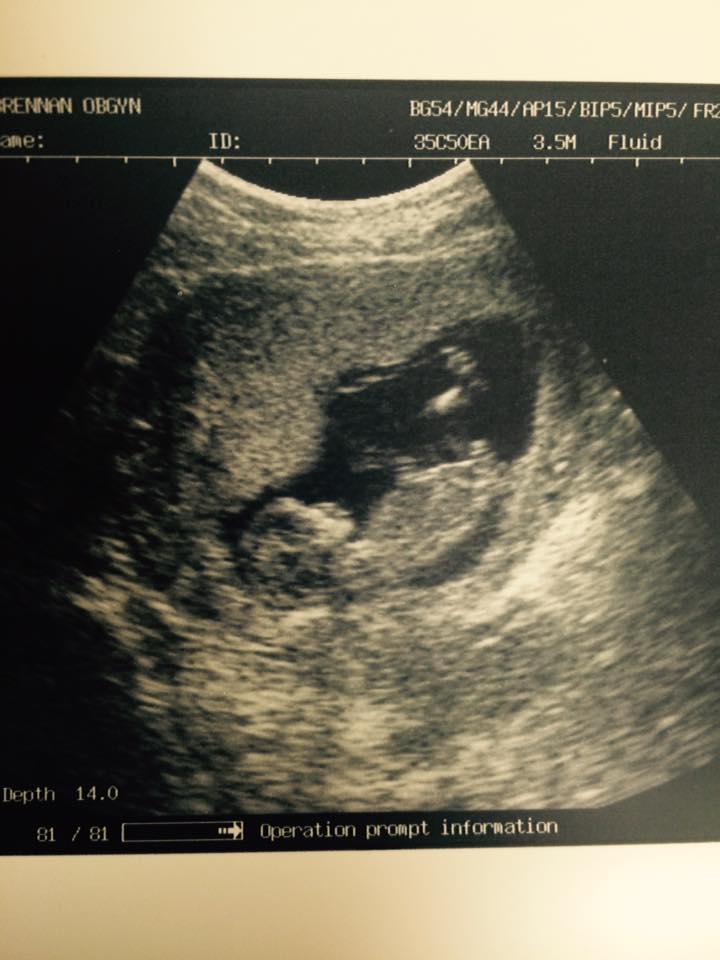

I think i know what it is.. but would love some opinions! :) Thank you! hopefully I attached this correctly.

EDIT: Does anyone have any reason to believe that that "stacked nub" may not in fact be a nub at all? I can honestly say I 100% do not mind either way if this baby is a boy or a girl (first time I have been able to say that with all my pregnancies) But I also dont want to get my heart set too much on boy if anyone has a doubt that it is. make sense? I know nub isn't going to be 100% accurate but mine is SO boyish it makes it hard not to get excited over blue!

So could someone reassure me that is definitely the nub and no chance its something else? lol!